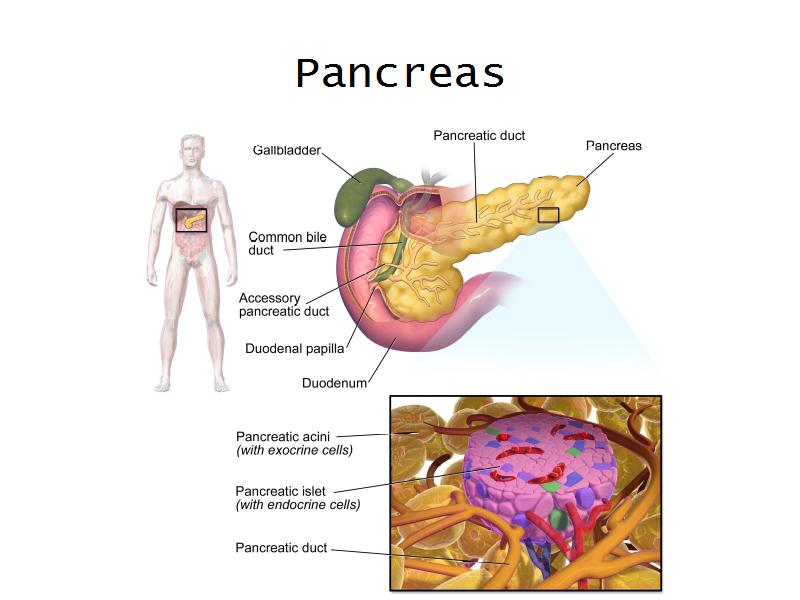

- Pancreas

- C3: Pancreas

- C3: Pancreas = glucagon, insulin, somatostatin, pancreatic polypeptide

- F4: Alpha cells = pancreas

- Slide 50: Pancreas